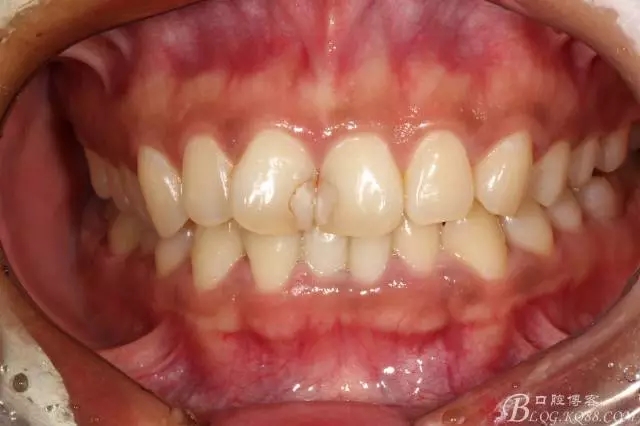

半年后(2016.9)復(fù)查照(這次復(fù)查已完全適應(yīng)修復(fù)后的效果,冷熱也不敏感了,我的心也就放下了)

修復(fù)前后效果對(duì)比照片(看前面的吧)

患者還是比較信任,希望能追蹤更長(zhǎng)期的效果。